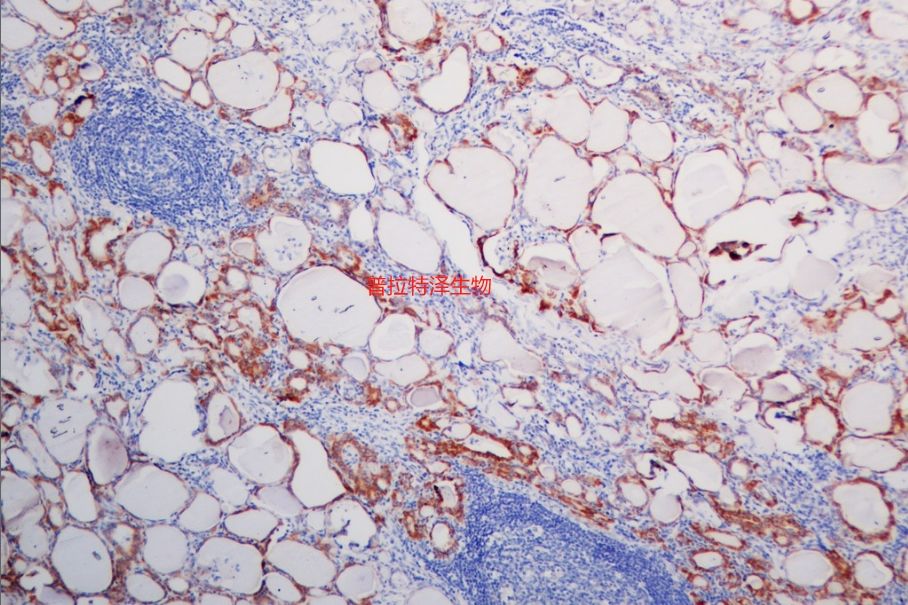

原位雜交是一種在細(xì)胞或組織水平上檢測特定核酸序列的技術(shù)。然而,在實際應(yīng)用中,原位雜交實驗常常會遇到一些問題,如非特異性染色、背景信號過高、假陽性或假陰性結(jié)果等。普拉特澤生物承接原位雜交等病理染色相關(guān)服務(wù)上萬例,積累了操作大量經(jīng)驗,為大家詳細(xì)分享原位雜交常見問題的分析與對策,同時為廣大科研工作者開展線上的理論培訓(xùn)與線下實操,可承接染色實驗外包服務(wù)。